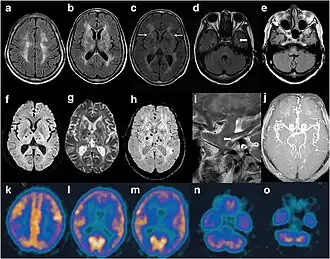

Exame de imagem de paciente com IFF. Na ressonância magnética, vê-se sinais anormais na área área subcortical frontoparietal bilateral. Resultados de exame de ressonância magnética angiográfica exibiram separações distais de artérias cerebrais